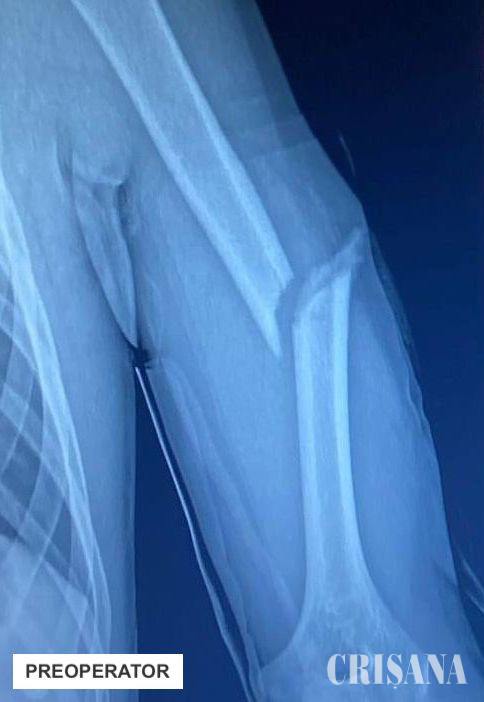

Un pacient în vârstă de 16 ani s-a prezentat la Spitalul Clinic Județean de Urgență Bihor cu o fractură diafiză humerală cu deplasare, în urma unui accident rutier. Osul lung al brațului (humerusul) era fracturat, iar cele două segmente erau deplasate de la locul lor. Adolescentul trebuia operat pentru repunerea la loc a fragmentelor osoase fracturate, soluțiile clasice pentru tratamentul ortopedic al fracturilor pediatrice implicând fie montarea unei plăci cu șuruburi, sau utilizarea tijelor elastice. În acest caz însă, din cauza vârstei de peste 15 ani, pacientul avea cartilajul de creștere închis, ceea ce reprezintă un factor de incompatibilitate cu variantele chirurgicale menționate.

Așadar, echipa operatorie a decis să efectueze, în premieră județeană, reducerea ortopedică închisă cu osteosinteză prin tijă zăvorâtă din titan pentru un pacient pediatric. Sub control radiologic, s-a efectuat reducerea ortopedică închisă a osului fracturat, iar apoi s-a introdus o tijă de titan pentru fixarea fragmentelor osoase.